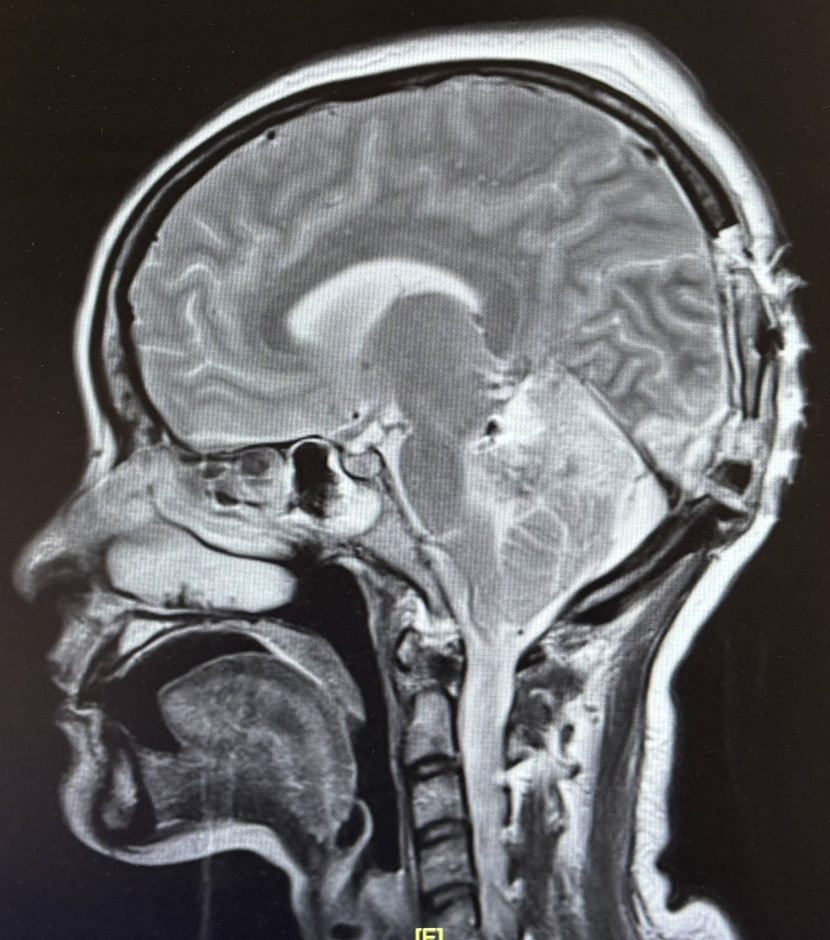

2期术前MRI